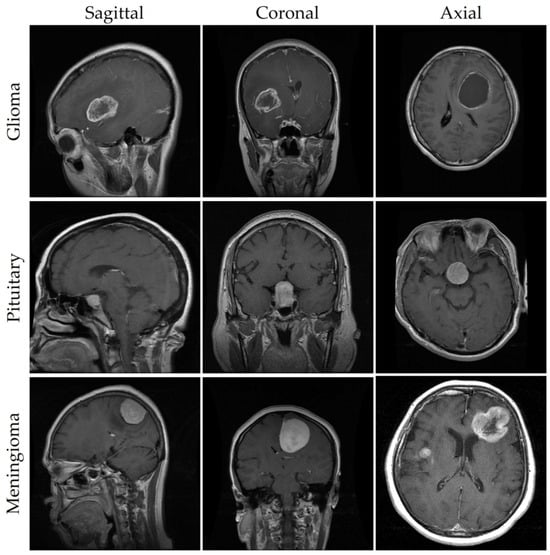

| Class | Coronal | Axial | Sagittal | Total |

|---|---|---|---|---|

| Meningioma | 232 | 208 | 268 | 708 |

| Glioma | 493 | 494 | 439 | 1426 |

| Pituitary | 321 | 291 | 318 | 930 |

| Total | 1046 | 993 | 1025 | 3064 |